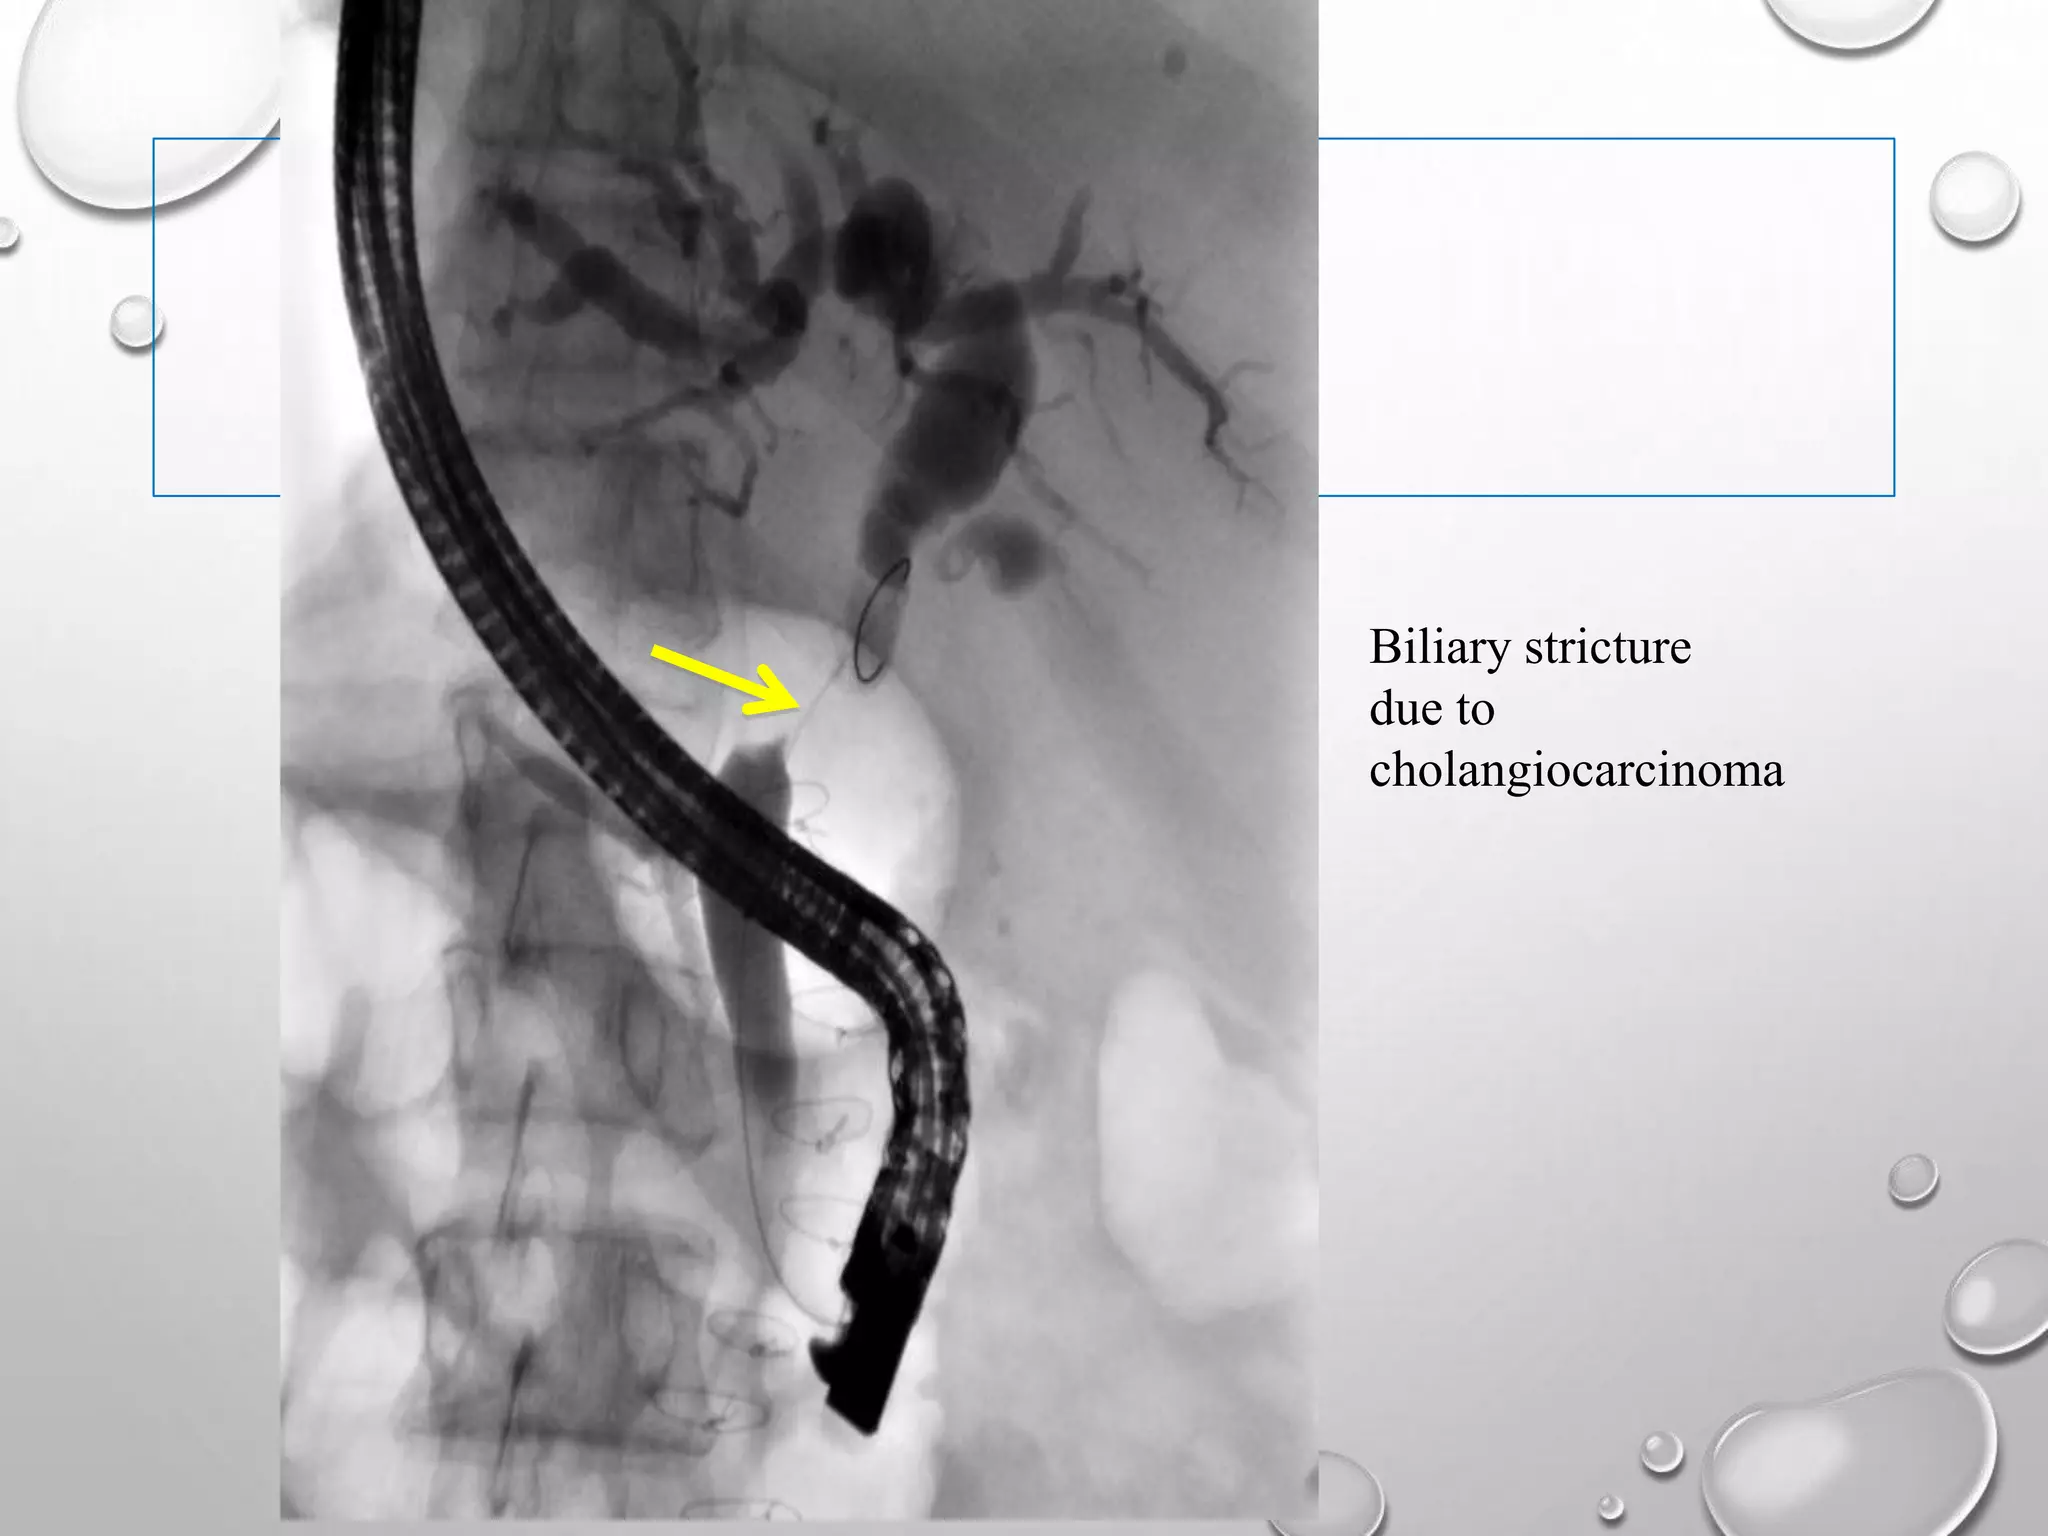

Biliary stricture

due to

cholangiocarcinoma

ERCP  89%-98% sensitivity& 89%-100% specificity.  ERCP is the procedure of choice in choledocholithiasis and in suspected ampullary or duodenal lesions in ca pancreas.  The diagnostic role of ERCP is to collect tissue for biopsy in periampullary growths or brush cytology samples. The exact level of the block and the severity of backpressure changes can also be ascertained.